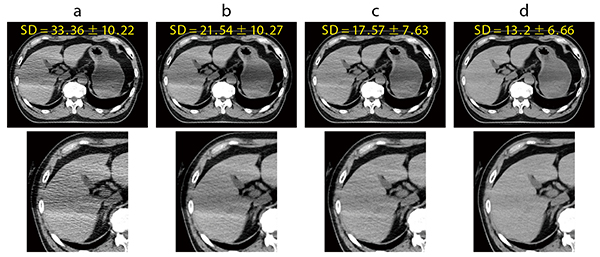

Aquilion Exceed LBでのAiCE-iの適用について平入係長は、「救急では、挙上できずに腕を下ろしたまま撮影することがありますが、以前は腕のアーチファクトの影響で画像が劣化していた腹部の肝臓などがAiCE-iの適用で画質が改善しています(図1)。また、従来より線量を下げた撮影プロトコールを組んでいますが、以前と同様に診断可能な画像を提供できているのはAiCE-iによるノイズ低減の効果だと思います」と説明する。

図1 AiCE-iの効果(上肢挙上不可能患者)

a:FBP

b:AIDR 3D

c:AIDR 3D Enhanced

d:AiCE-i

*AIDR 3D=Adaptive Iterative Dose Reduction 3D